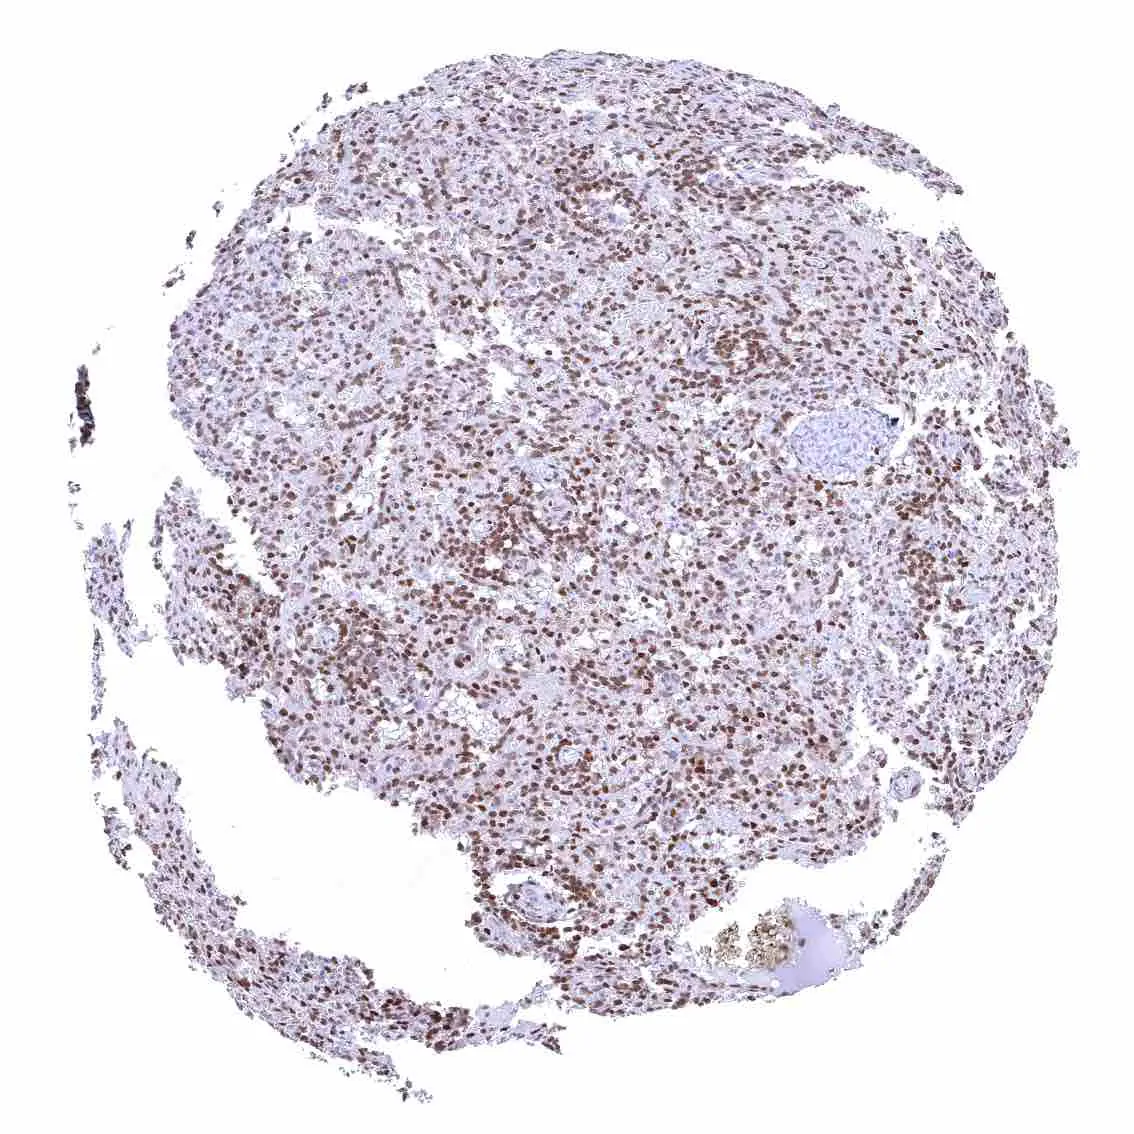

Spleen – Strong nuclear p27 staining of a large fraction of cells.